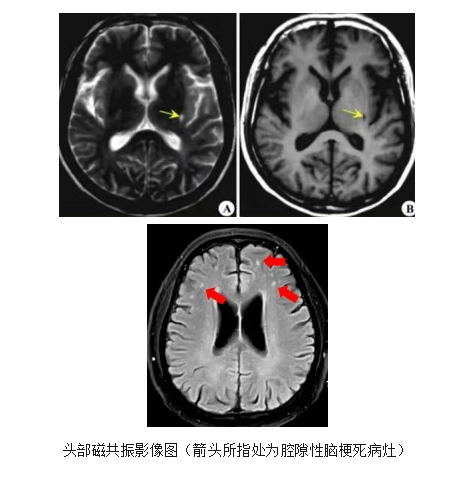

【健康科普】什么是腔隙性脑梗死,一文为您讲清楚

腔隙性脑梗死是一种常见的脑梗死类型,据统计,60岁以上的人群腔隙性脑梗死的发病率高达50%,且在患有高血压,糖尿病,高血脂等基础疾病的人群中更为多见。其病变范围一般为2-15毫米,其中以2-4毫米者最为多见,一般来说,绝大多数腔隙性脑梗死不会有临床症状,也不会出现失语、偏瘫、感觉障碍等体征,这是因为腔隙性脑梗死病变的血管供血区面积很小,受累脑组织很少,故而不会出现明显的临床症状,因此很多人是做头部CT或磁共振才意外发现。但是,反复多发性的腔隙性脑梗死,经过数量上的积累,会导致大脑出现不可逆转的变化,导致大脑功能下降,最后出现痴呆的症状。